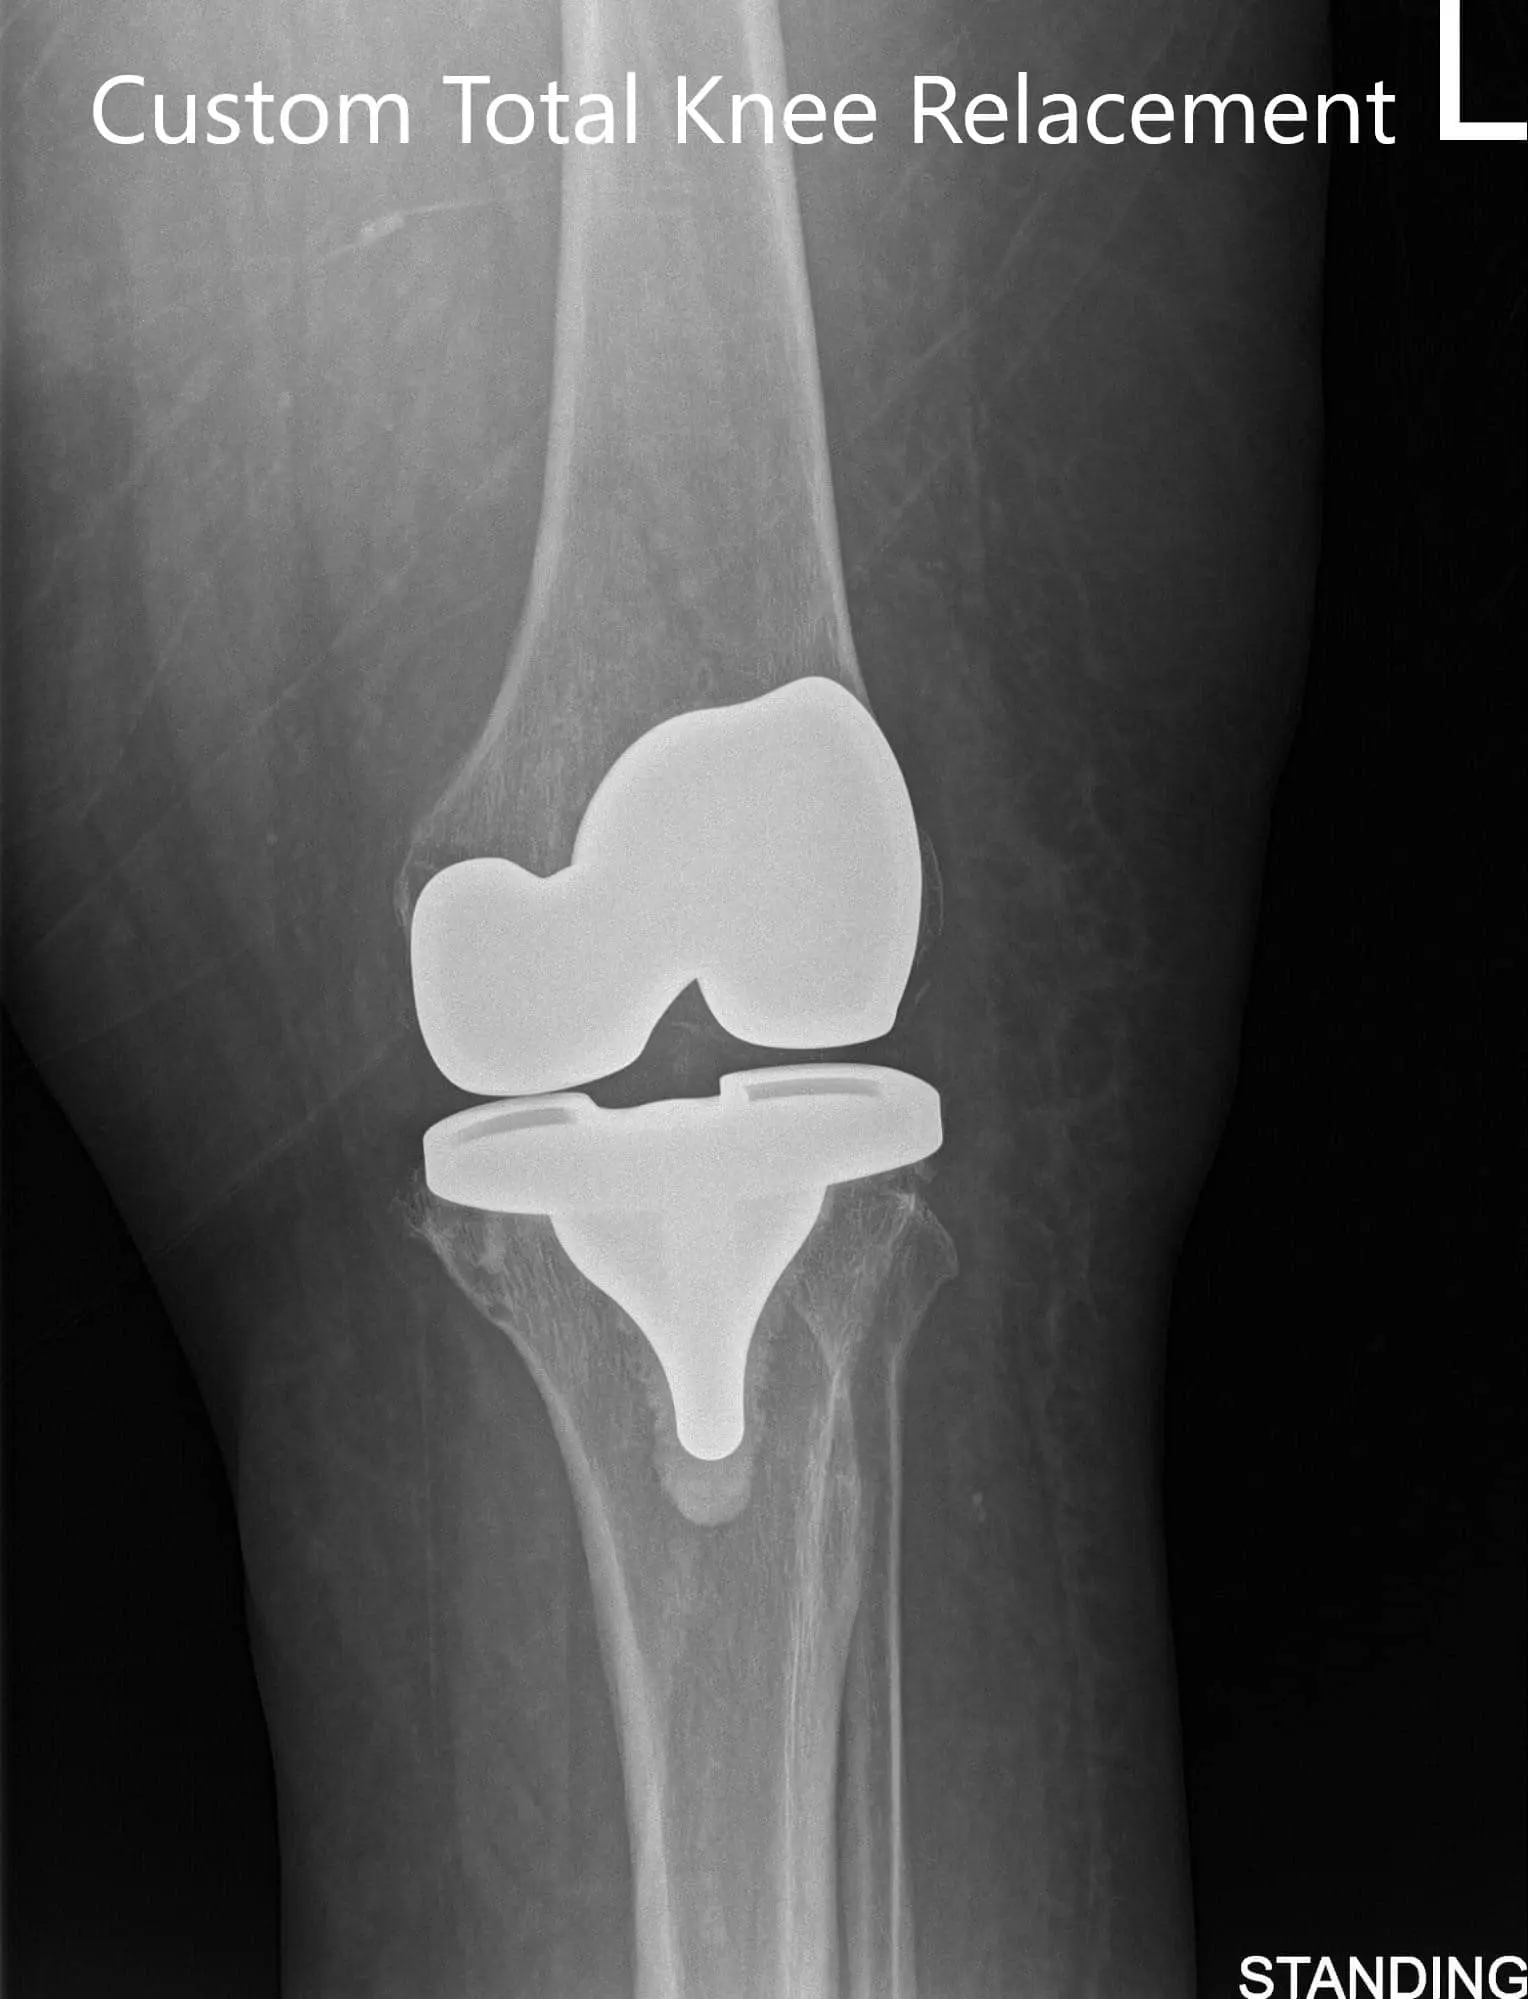

Postoperative X-ray showing AP and lateral images of the left knee